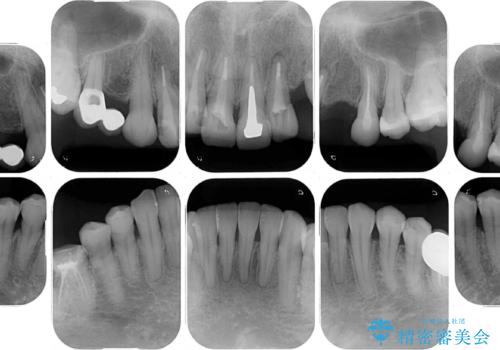

- 他院で矯正治療を終えたものの、むし歯や欠損部の治療が進められないとのことで来院された患者様です。

欠損部や、銀歯やむし歯の大きな歯はセラミッククラウンやブリッジに、小さいむし歯はセラミックインレーにて治療を行うこととしました。